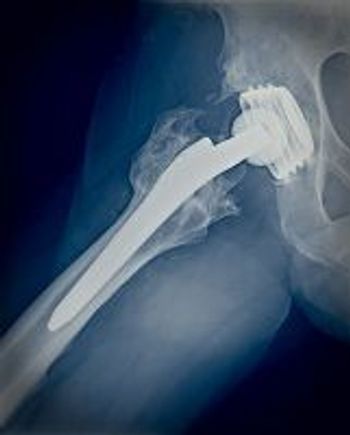

Inflammatory bowel disease patients can be afflicted by various forms of arthritis from peripheral arthritis to ankylosing spondylitis and symmetrical polyarthritis. In this slideshow, we address identification, diagnosis and treatment for these complex cases.